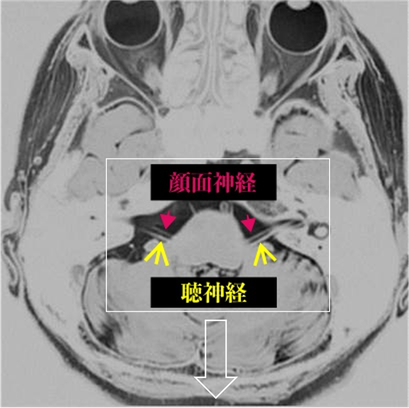

頭部MRI検査にて頭蓋骨内の顔面神経の走行を確認する事ができます。これによる画像情報と臨床的な経過や症状から診断します。

【 頭部MRI画像による頭蓋骨内の顔面神経の走行 】

(写真上)

頭の断面MRI画像です。顔面神経は、聴神経(耳で聞いた音を脳へ伝える神経)と併走しています。これらの神経は、2本線として認めらています。

(写真下)

問題となる場所は、脳から顔面神経(点線↑)が出た部位神経根部(*)です。拍動する血管(動脈)が顔面神経根部(*)を圧迫する事が主な原因になります。稀に脳腫瘍が顔面神経を圧迫する事により痙攣(けいれん)を誘発させていることもあります。脳の表面や頭蓋骨内側に存在するクモ膜や拍動しない血管(静脈)が原因となる事もあります。血管や腫瘍などの圧迫により刺激を受けると顔面の筋緊張が高まり(顔がこわばる、眼が開きにくいなどの症状)、顔面の痙攣(けいれん)を誘発させるようになります。

----------------------------------------------------------------------------------------------------------------------------

顔面神経の下を走行している神経は聴神経(耳から聞いた音を脳に伝える神経)です。